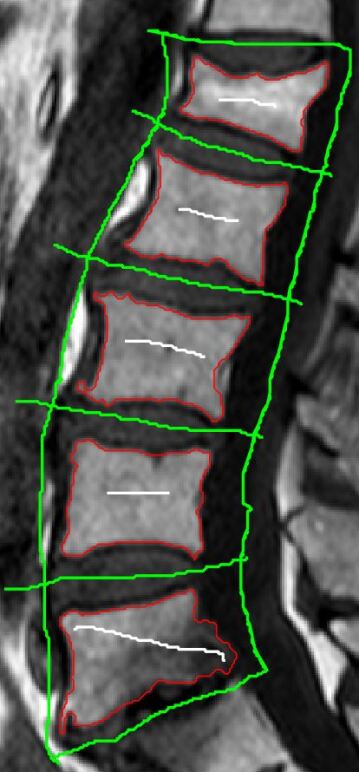

The balance induced by the weights produces smoother borders at regions with small pixel intensities. Moreover, as long as the interior annotation contains small portions of the dark and bright regions, it can work well even with rough interior and exterior seed points. To better illustrate this, Figure 3 shows a few iterations of BGrowth for a single vertebral body segmentation. Note that, at iteration 5, a few dark regions (outside of the vertebral body) are still part of the foreground and, as the balancing goes on, the foreground shrinks towards the ground-truth. The final result is quite close to the manual segmentation. Figure 4 shows another example of BGrowth’s iterations on five lumbar vertebrae. Note that, the method works quite well even when a simple line is given as seed points. The only constraint is that the interior annotation has to comprise the dark/bright regions within the vertebral body.

![]() |

| Annotations | Iteration 1 | Iteration 5 |

| Iteration 10 | Iteration 20 | Iteration 50 |

As we work with the balance of old and new strength factors, it might happen that the process of expansion goes back and forth on the same pixel. Therefore, we would recommend the definition of a maximum number of iterations depending on the kind of image being segmented. We have empirically used a maximum of 30 iterations for the segmentation of a single vertebral body. For a whole exam, as exemplified in Figure 4, a few more iterations might be necessary.